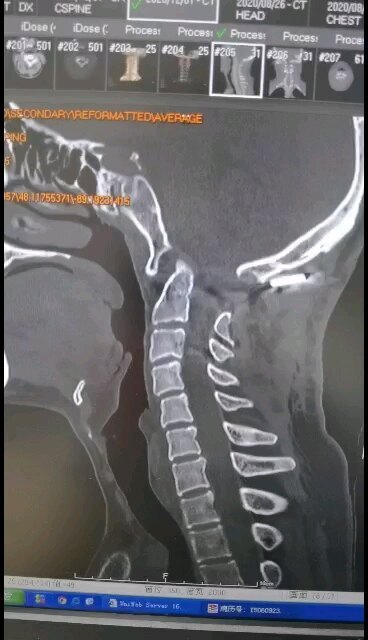

脊髓空洞,小脑扁桃体下疝畸形

牛建星主任医师 航空总医院 神经外科分院

脊髓空洞症,小脑扁桃体下疝畸形

小脑扁桃体下疝畸形,脊髓空洞症,寰枕畸形